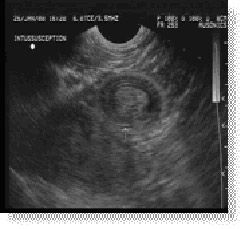

Abdominal pain in the foal can be a frustrating diagnostic challenge as the differential diagnosis are extensive.